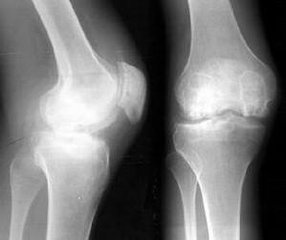

膝关节骨质增生药物治疗方案。膝关节骨质增生患者若有局限性压痛,可进行局部药物注射治疗。由骨科医师亲自注射,力求一针解除病痛。>>>点击此处,专家一对一为您详解骨质增生

代表疗法:液体刀疗法、玻璃酸钠注射以及臭氧关节腔内注射等。